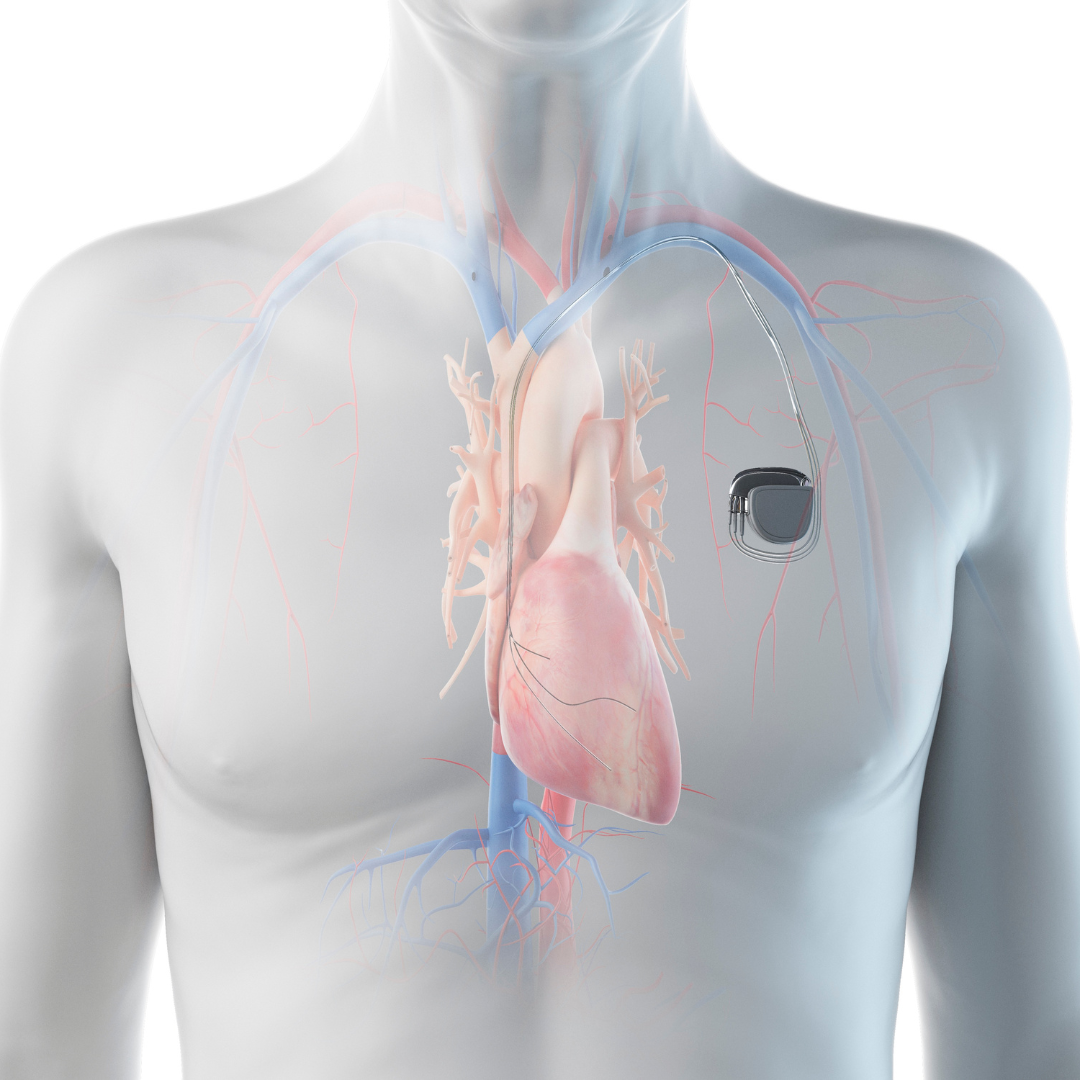

Pacemaker

A procedure that places a small device to regulate slow or irregular heartbeats, helping maintain a normal heart rhythm and improve overall heart function.